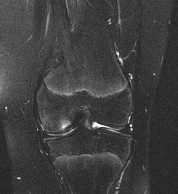

Question 1:

A 45-year-old recreational athlete presents with acute medial knee pain after feeling a 'pop' while deep squatting. MRI demonstrates an extrusion of the medial meniscus of 4 mm and a complete radial tear at the posterior root. Which of the following best describes the primary biomechanical consequence of this specific injury pattern?

Correct Answer: Loss of hoop stresses leading to peak contact pressures equivalent to a total meniscectomy

Explanation:

A posterior medial meniscus root tear disrupts the circumferential hoop stresses that the intact meniscus relies on to dissipate axial loads. Biomechanical studies demonstrate that a posterior root tear is functionally equivalent to a total meniscectomy in terms of decreasing contact area and dramatically increasing peak tibiofemoral contact pressures, leading to rapid chondrolysis and osteoarthritis if left untreated.